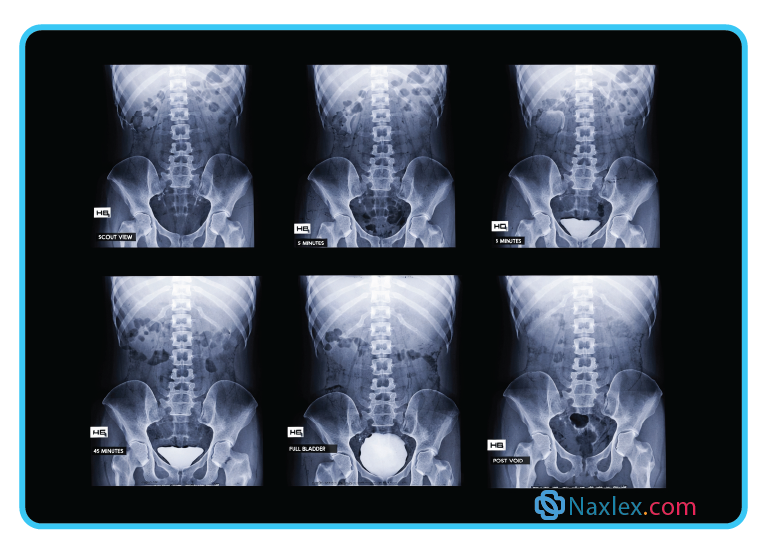

An Intravenous pyelogram (IVP) is an X-ray imaging test used to evaluate the urinary tract - including the kidneys, ureters, and bladder - by injecting a contrast dye into a vein, which highlights these structures as it flows through them. The procedure helps doctors assess the shape, size, and function of the urinary system and detect problems such as kidney stones, tumors, urinary tract blockages, infections, or congenital abnormalities.

Rationale for correct answer:

1. Ask about allergies: An IVP involves injecting radiopaque contrast dye, which often contains iodine. The nurse must assess for allergies to iodine, shellfish, or previous reactions to contrast media to prevent anaphylaxis.

4. Informed consent: Since the procedure involves the injection of a contrast medium and carries risks (allergic reaction, kidney stress), the nurse must verify that the physician has explained the risks and the client has signed the consent form.

5. Facial flushing: It is a common, non-allergic side effect for clients to feel a sudden sensation of warmth, facial flushing, or a metallic taste in the mouth immediately after the dye is injected. Warning the client prevents anxiety during the test.

Rationale for incorrect answers:

2. Full bladder required: Unlike a pelvic ultrasound, an IVP does not require a full bladder. In fact, the client is usually asked to void before the procedure to ensure the bladder doesn't obstruct the view of the pelvic structures.

3. Save all urine: This is a requirement for a 24-hour urine collection, not an IVP. There is no need to save urine samples prior to this imaging test.